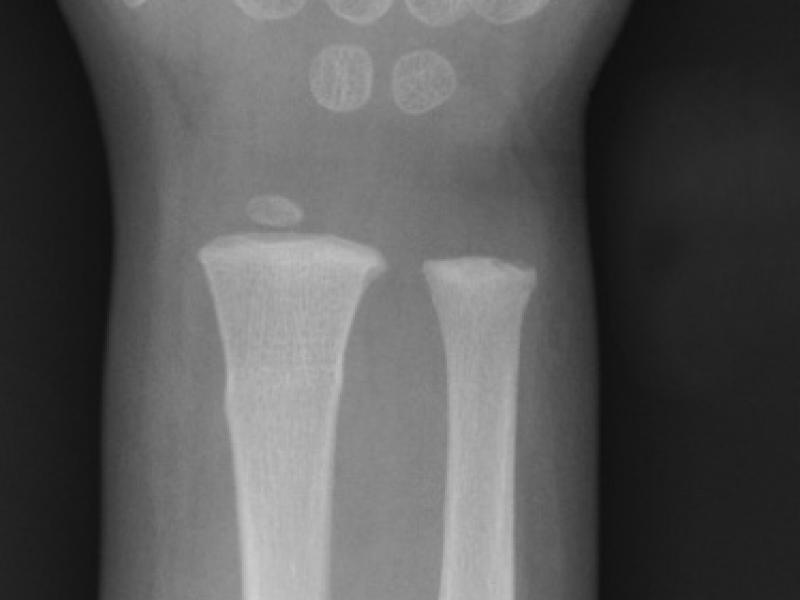

What's the diagnosis?  By Dr. Loran Hatch

January 23 2019

A 2 yo male presents to the ED with his mother because she

EM Daily